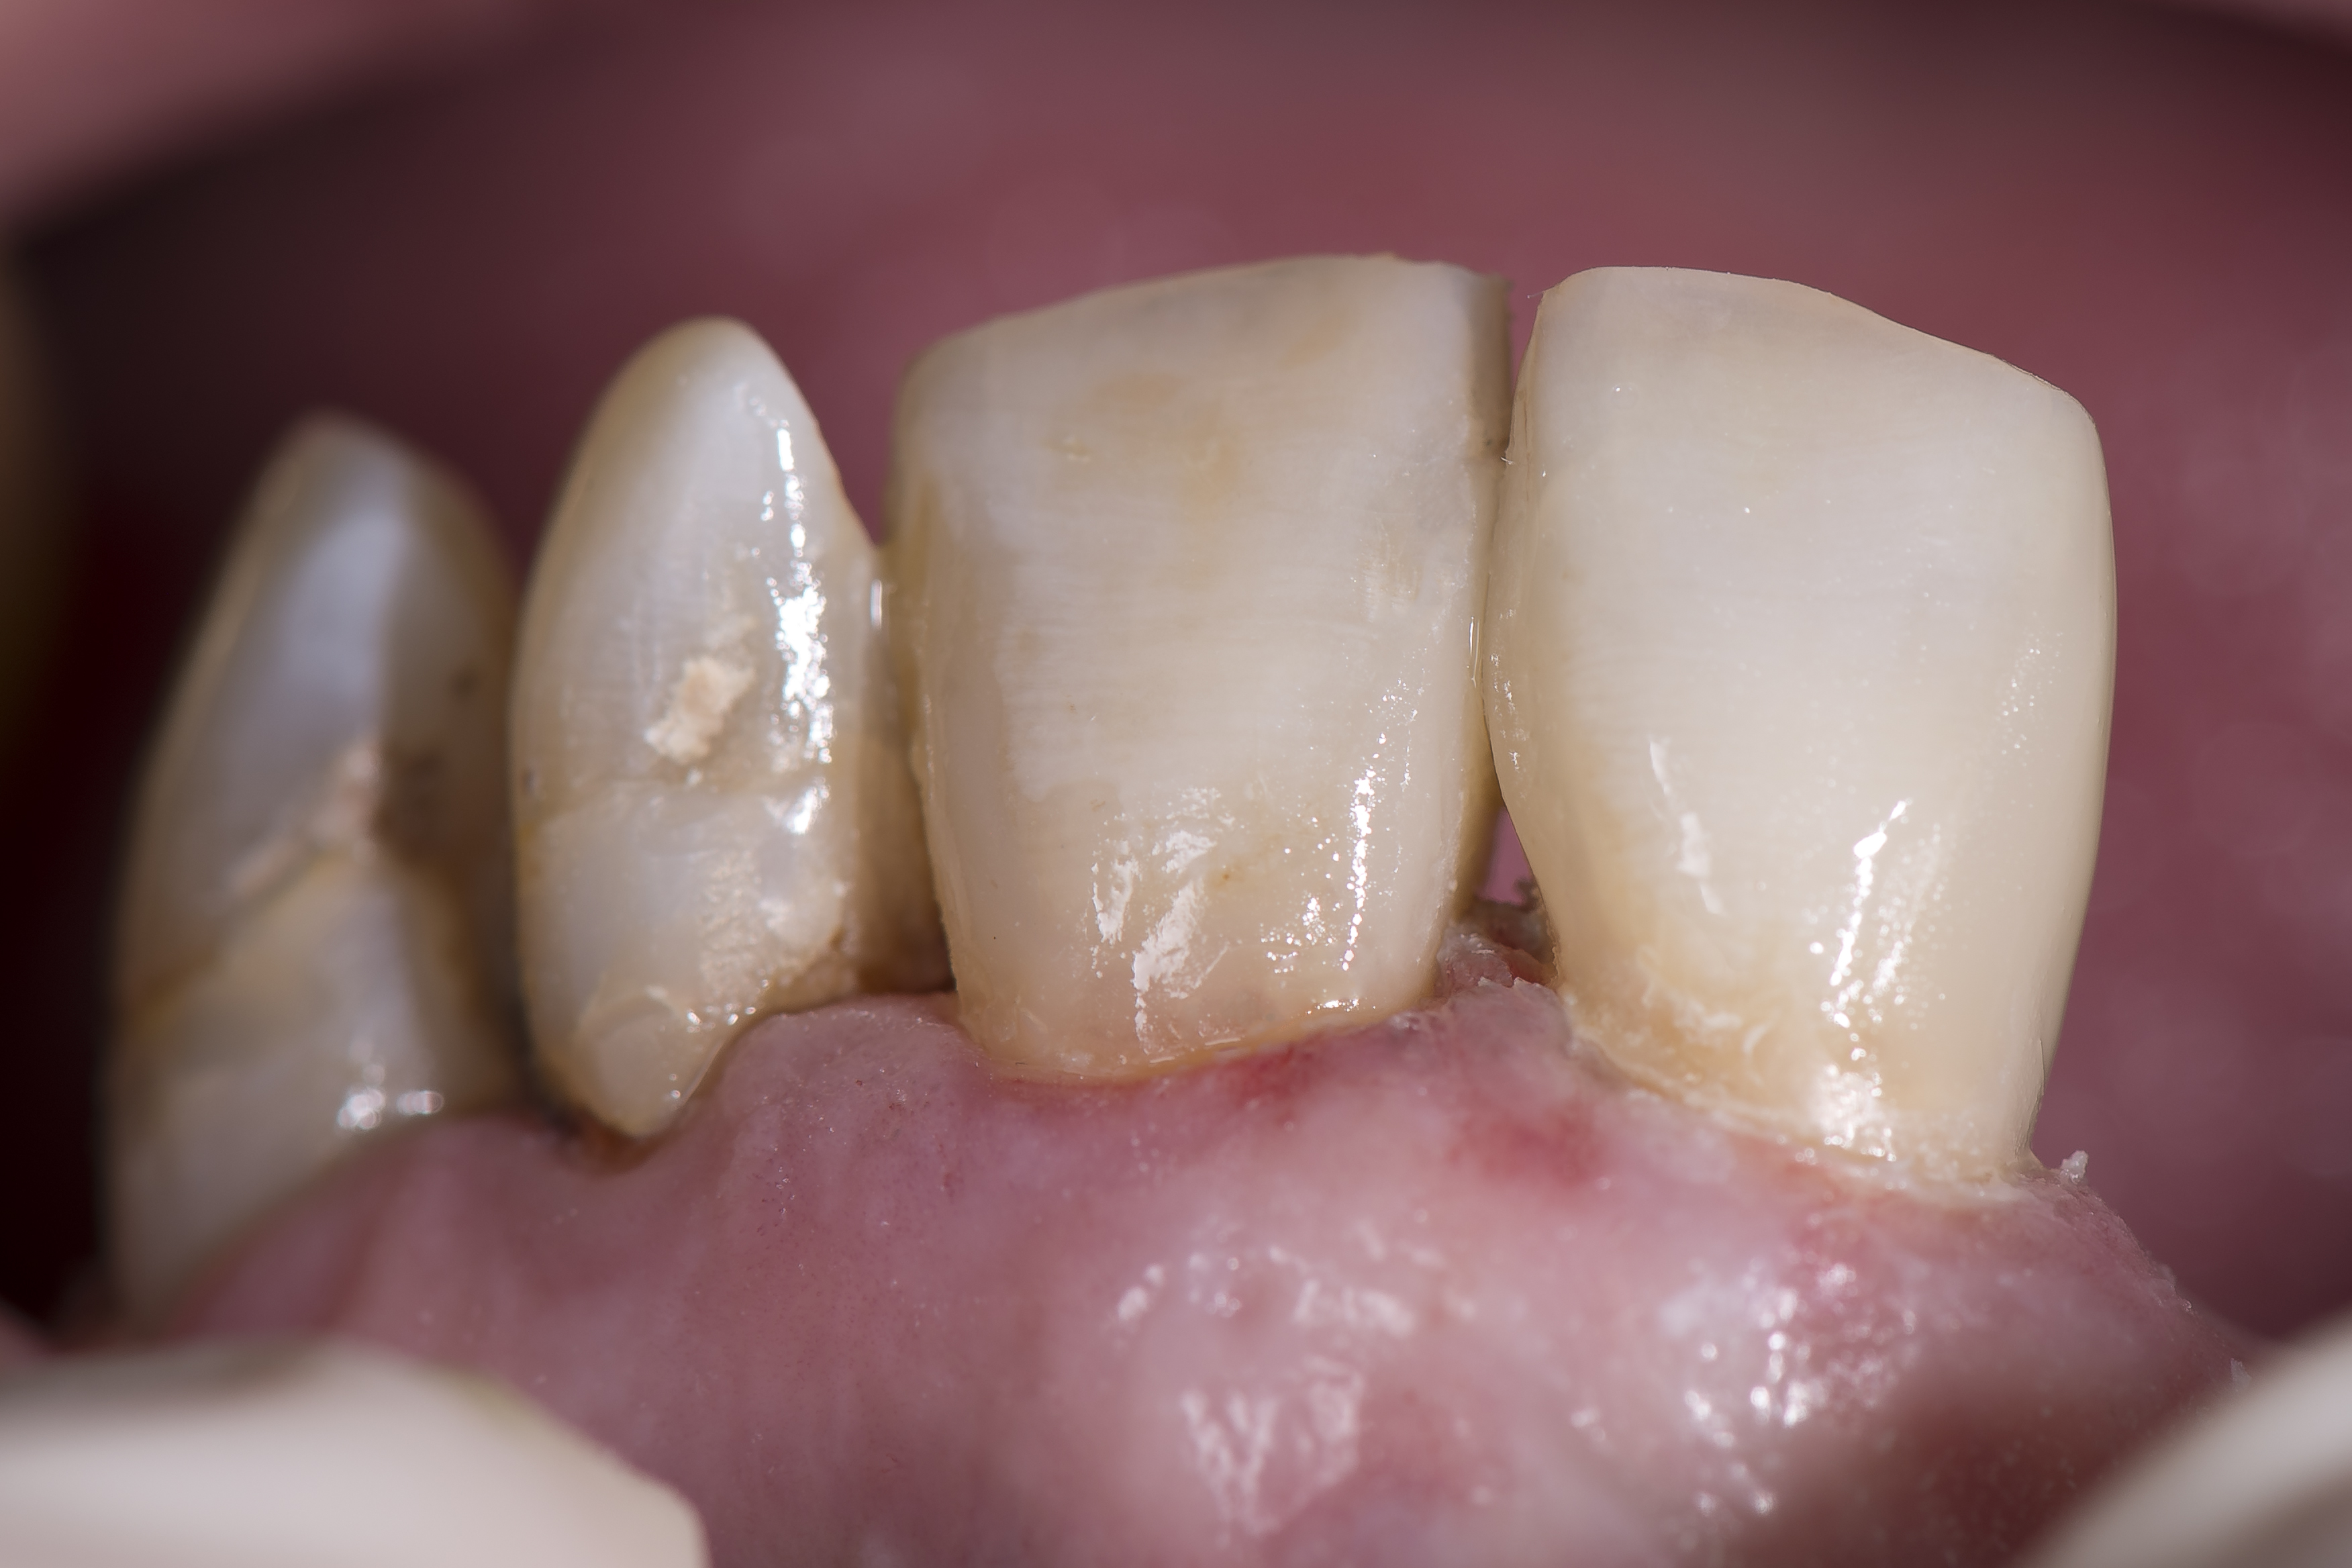

Po skończonej polimeryzacji każde wypełnienie było poddane kontroli i ewentualnemu dostosowaniu do warunków zwarciowych – co nie było zbyt problematyczne, biorąc pod uwagę umiejscowienie ubytków. Ostatnim etapem było polerowanie przy pomocy gumek Opti1Step oraz szczoteczek polerujących OccluBrush (Kerr) (ryc. 12).

Ryc. 12. Na zdjęciu widocznych jest ogółem sześć wypełnień kompozytowych wykonanych jednym odcieniem materiału kompozytowego w różnych miejscach różnych zębów i w ubytkach o różnym kształcie i głębokości.